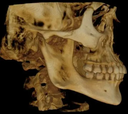

The ultimate in versatility, the CS 9300 system combines dedicated panoramic, optional one-shot cephalometric and up to 7 selectable fields of view cone beam 3D images for the widest range of dental applications.

3D - The innovative CS 9300 delivers crystal-clear, high-quality 3D/CBCT images in seconds. Choose from a variety of fields of view, including Focused, Single/Dual Jaw, TMJ (2x and 4x), Sinus, and Maxillofacial options. The included CS 3D Imaging software enhances treatment planning and facilitates patient communication.

Adjustable Fov - CS 9300 captures a wide range of field of view sizes (5x5, 10x5, 8x8, 10x10 cm) to support a variety of dental applications - from single implants to complete maxillofacial exams.